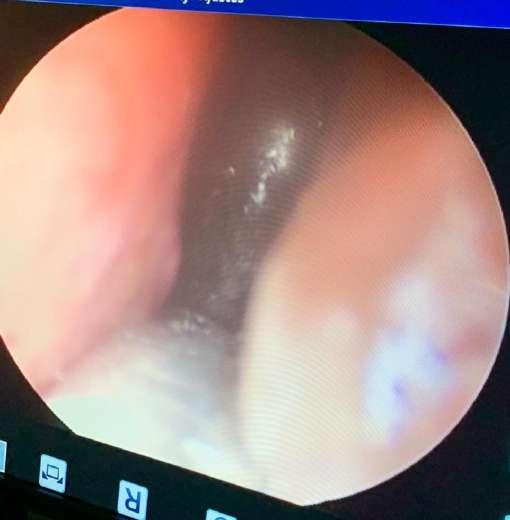

Caso aportado por Dr. Tomás Gonzáles y Nathan Dukes

ü Hombre 19 años portador de Leucemia linfatica aguda diagnosticada el 2016, es tratado ese mismo año con trasplante alogénico, sin embargo 4 meses posterior al trasplante sufre una recaída leucémica. Desde entonces el paciente se ha mantenido en QMT sistémica paliativa

ü El año 2017 el paciente evoluciona con enfermedad injerto contra huesped y el 2018 con meningitis leucémica

ü El año 2019 consulta en el policlínico de oftalmología del Hospital del Salvador por disminución de AV ODI de 7 dias evolución, asociado a sensación de cuerpo extraño.

Examen Físico

ü AV con CAE: 20/70 OD y 20/60 OI

ü PIO normal bilateral

ü DPAR en OD

ü Motilidad ocular conservada.

ü BMC: Puntata extensa como consecuencia de efectos adversos producidos por la QMT (Imagen A y B) A